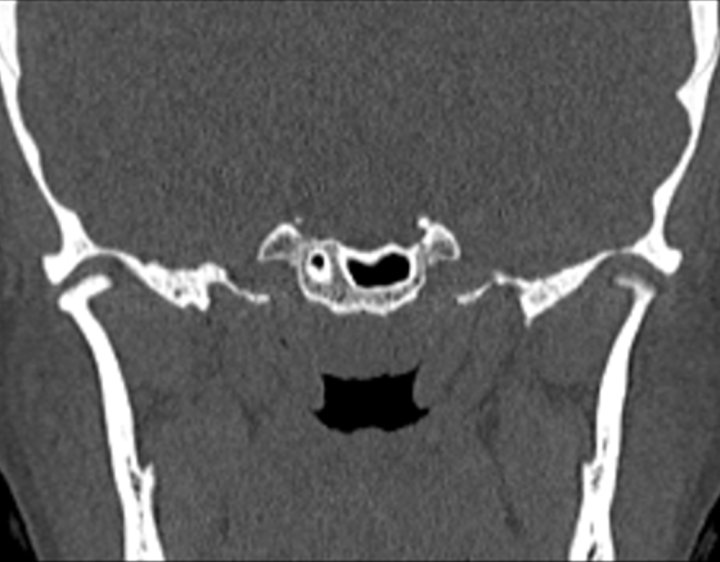

Click any image for labels.